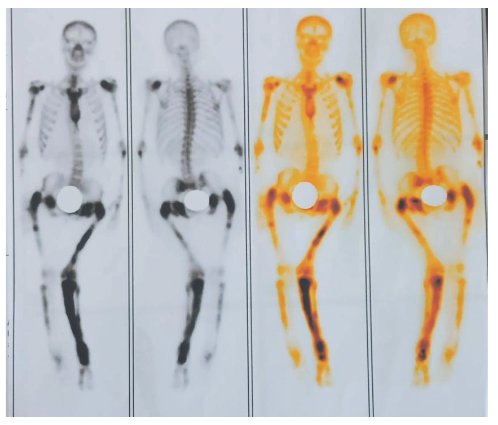

Nuclear bone scintigraphy is the most sensitive test for identifying pagetic lesions. (7) Regarding laboratory tests, several markers of elevated bone turnover can be used; among these, serum alkaline phosphatase (AP) is the most commonly used. (12)

Figure 6. Bone scan: marked increase in osteoblastic activity with bone deformity in the humerus, femur, tibia, which appears to correspond to the scintigraphic pattern of Paget's disease as a first consideration.